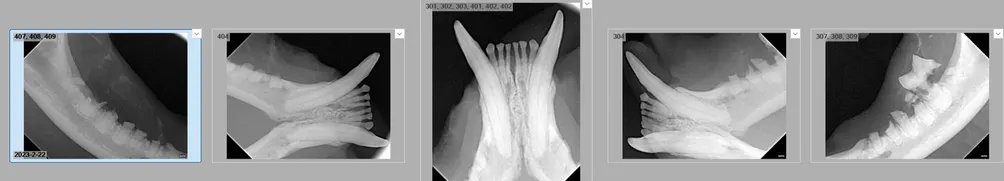

牙起來! 犬貓口腔大小事。

狗狗貓貓沒有牙齒,還可以正常吃飯嗎

" 牠已經嚴重發炎了,媽媽,這些牙齒恐怖只能拔掉,再拖下去不是辦法....." 門診中時常遇到口腔狀況非常糟糕的犬貓,而這些犬貓的共通點: 飼主實在受不了口臭 滿口佈滿的牙結石 嘴邊的毛髮十分雜亂,混合散發惡臭的口水 可能非常抗拒觸碰嘴巴 (疼痛!) 通常年紀都不小 面對這樣的問題,通常必須花非

犬貓無麻醉洗牙可以嗎

無麻醉洗牙到底可不可以,無麻醉聽起來好像很安全?

犬貓乳牙該不該拔?

乳牙問題看似小,但實質上影響很多,有很多要注意的喔

不完美的牙齒缺角: 犬貓補牙

iphone蘋果的缺一角象徵著不完美,需要每天進步。 動物牙齒的缺一角象徵著不單純,需要來檢查牙齒囉